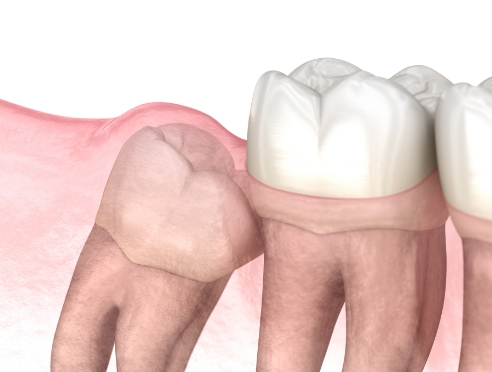

在通过锥形束CT精细确认智齿方向,

神经位置及与邻牙关系后,

仅在

确有必要的情况下才进行拔除

采用最大程度减少组

织损伤的方式来降低负担,

帮助患者更轻松地完成术后恢复